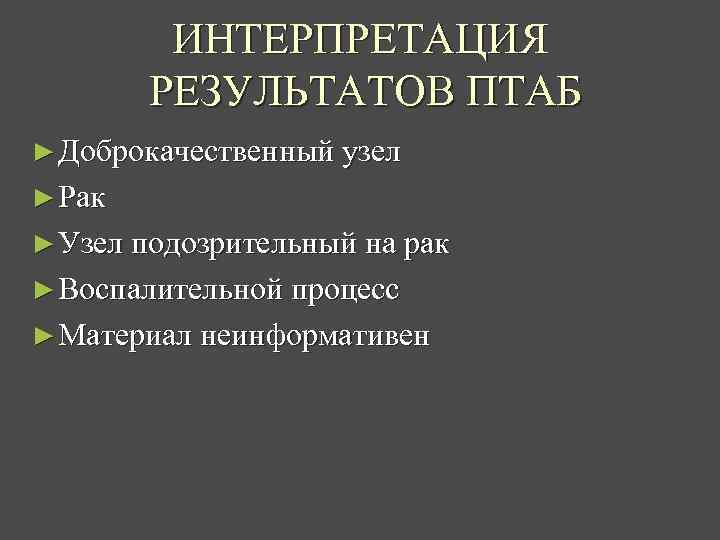

ИНТЕРПРЕТАЦИЯ РЕЗУЛЬТАТОВ ПТАБ ► Доброкачественный узел ► Рак ► Узел подозрительный на рак ► Воспалительной процесс ► Материал неинформативен